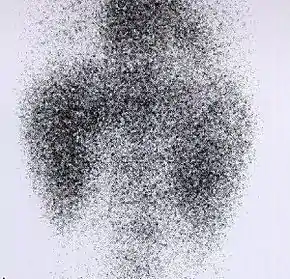

DMSA scan

![]() Decreased Tc99m-DMSA uptake in both kidneys, suggestive of renal failure. | |

A DMSA scan is a radionuclide scan that uses dimercaptosuccinic acid (DMSA) in assessing renal morphology, structure and function. Radioactive technetium-99m is combined with DMSA and injected into a patient, followed by imaging with a gamma camera after 2-3 hours.[1] A DMSA scan is usually static imaging, while other radiotracers like DTPA and MAG3 are usually used for dynamic imaging to assess renal excretion.[2]